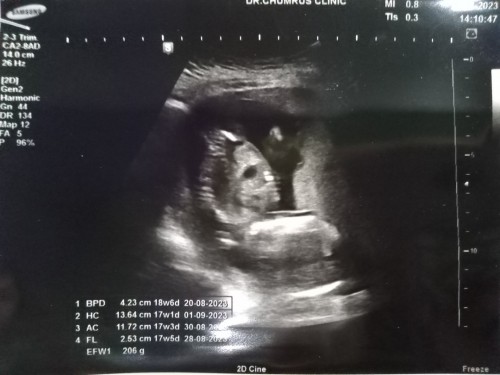

ท้อง18วิคแล้วค่ะ แม่ท่านไหนท้องโตแล้วบ้างคะ บ้านนี้ยังไม่โตเลย และเหนี่ยวเหมือนคนไม่ท้องเลยค่ะ

บ้านนี้18wท้องเริ่มออกแล้วค่ะ เริ่มรู้สึกน้องดิ้นเบาๆตอน16w